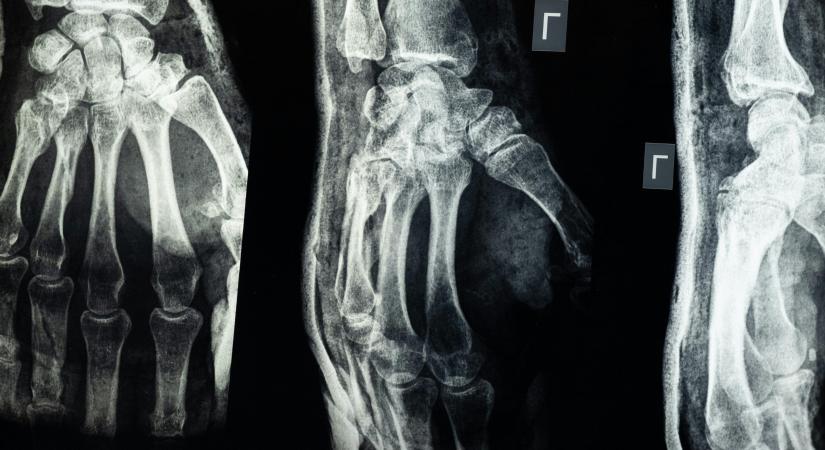

A munka során a „nagyfeszültségű elektromossággal előállított kathod sugarakra merőlegesen elég vastag és a fényre nézve áthatolhatatlan fekete papirosba burkolt érzékeny lemezt állítottak. Ezen papírburkolatra egy ezüst forintost, egy kulcsot és egy húszfillérest helyeztek oly képpen, hogy a légüres csőben keletkezett Röntgen-sugaraknak e tárgyakon át kellett menniük. Öt percig tartó exponálás után az amateur fotográfus Átlátszó kezek